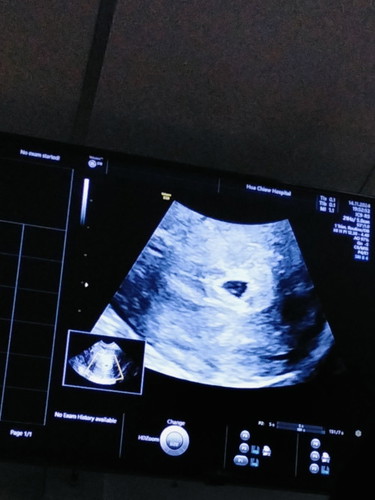

ประจำเดือนขาดตรวจครรภ์แล้วพบว่าท้องได้6สัปดาห์หลังจากตรวจวันที่11 ปัจจุบัน21 มีเลือดไหลออกมาคุณหมอฉีดยากันแท้งให้1เข็มบ้านไหนเคยเป็นบ้างคะ